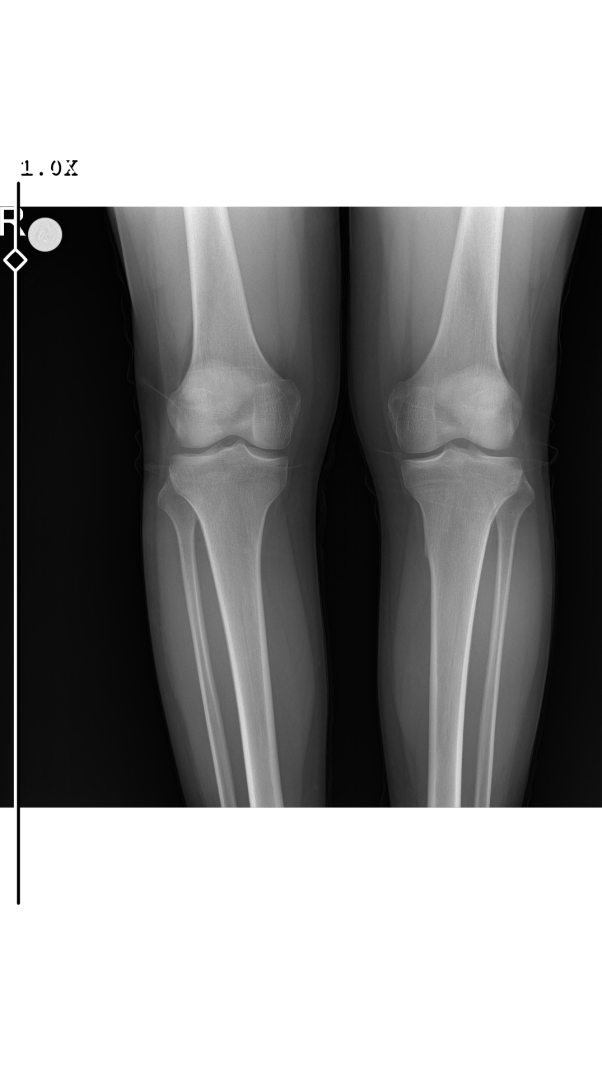

Arkadaşlar 14 yasindayim. Boyum 160 kilom 50 son 2 senedir cok az uzadim 5.sinıfda 140'dim. 7. sinifda 148'dim 8 de 158 şu an 9. sınıfım 160 fakat karantina doneminde ben gunde 1 ogun yiyordum. Yaklasik 600 700 kalori aliyordum. Beslenmem yetersizdi. Annem 160 babam 173 dayim 172/ben 160'im yasim 14 erkegim. Plaklarima bakar misiniz?

Benimkiler kapanmış mı bakabilir misin lütfen